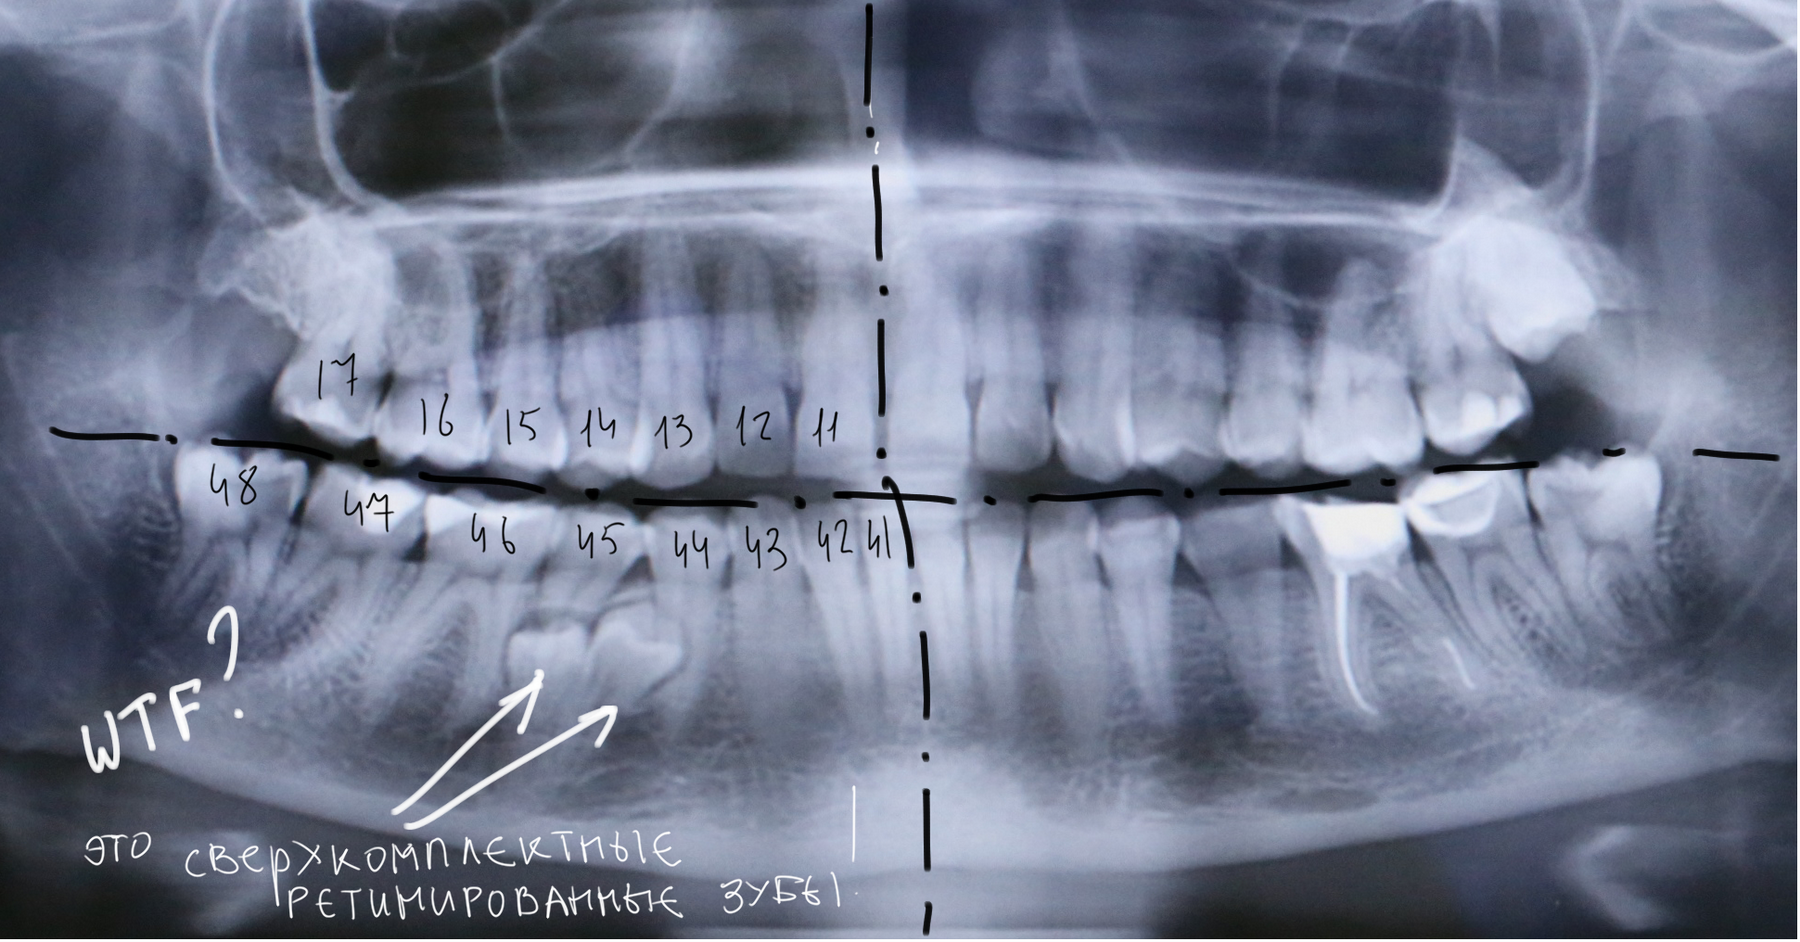

У моей пациентки случайно мы обнаружили два ретинированных сверхкомплектных премоляра:

При этом, весь комплект зубов на месте (за исключением правой верхней восьмерки — моя работа).

Вот разбор снимка: